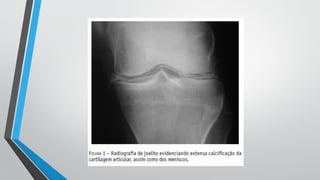

Doença por Pirofosfato – Diagnóstico

•Radiológico

• Calcificação, geralmente linear na fibrocartilagem ou cartilagem

articular